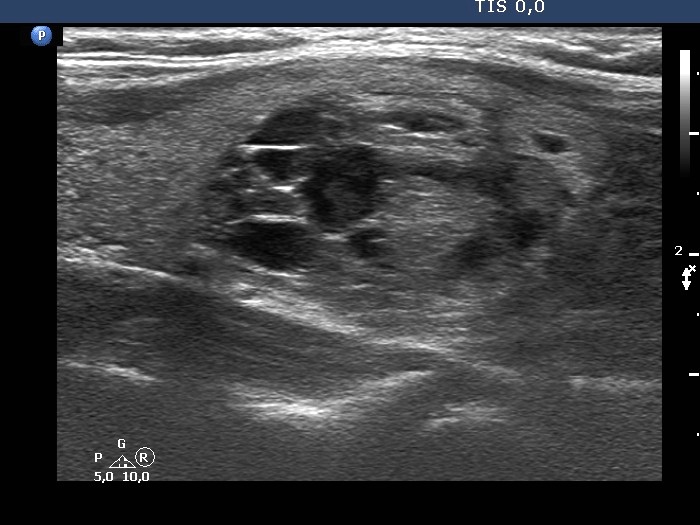

The composition of the nodule - case 142

Examination 3 years later (ultrasonographic picture 10)

Left lobe, another longitudinal scan.